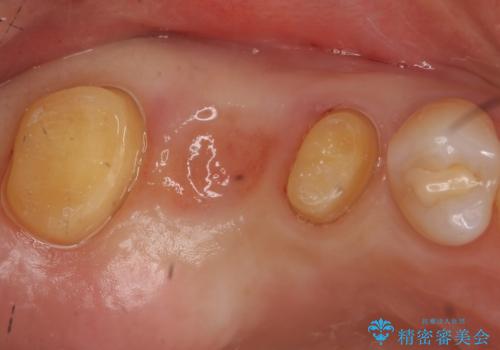

抜歯後そのままブリッジを入れるとブリッジと歯茎の間に大きなすき間ができてしまいます。その結果食べ物がつまりやすくなったり、息もれが生じたりと日常生活に支障をきたしてしまうことがあります。

抜歯後に骨を増やしてあげることで、ブリッジと歯茎との間にすき間が生じにくくなり、適合の良いブリッジを入れることが可能となります。